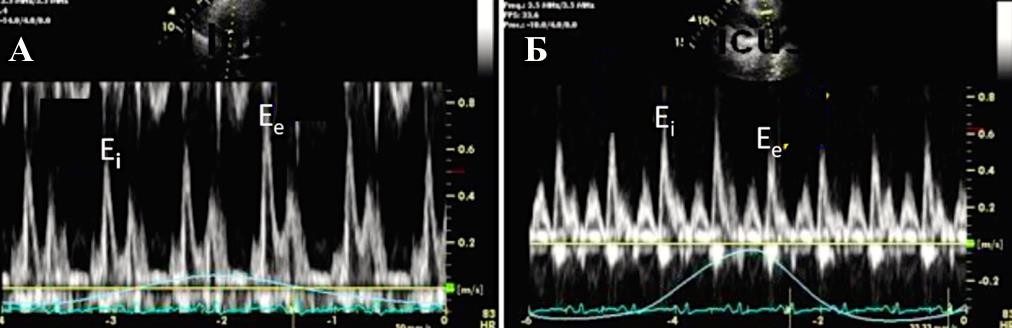

Парадоксальное движение межжелудочковой перегородки во время ранней диастолы является характерным для пациентов с констриктивным перикардитом. Во время вдоха движение происходит в сторону левого желудочка, во время выдоха — в противоположном направлении [3]. При М-модальном исследовании это проявляется выемкой в раннюю диастолу при определении движения межжелудочковой перегородки, что напоминает нарушения сокращения-расслабления миокарда, наблюдаемые при блокаде левой ножки пучка Гиса или электростимуляции правого желудочка (Приложение А3, рис. 5). При определении этого признака двухмерной ЭхоКГ чувствительность составляет 62%, а специфичность — 93% [3]. Использование допплеровской визуализации тканей можно существенно увеличить чувствительность метода до 82,5% [122].

Допплер-ЭхоКГ позволяет определить парадокс кольца. Он заключается в том, что при относительном сохранении способности миокарда растягиваться в продольном направлении деформация продольной оси левого желудочка и продольная ранняя диастолическая скорость либо нормальные, либо, по мере прогрессирования констриктивного перикардита, увеличиваются. В то время как при рестриктивной кардиомиопатии или при заболеваниях миокарда происходит снижение этих показателей. При этом усредненная максимальная тканевая скорость раннего диастолического смещения септальной части митрального кольца выше латеральной (Приложение А3, рис. 6) [117, 123, 124–128]. Несмотря на высокую чувствительность и специфичность (95% и 96% соответственно), ограничение данного признака при диагностике будет проявляться в случае неоднородности поражения перикарда или при кальцификации кольца митрального клапана.

Характерно динамическое изменение атриовентрикулярного кровотока в зависимости от фазы дыхания (Приложение А3, рис. 7), что отличает констриктивный перикардит от рестриктивной кардиомиопатии. На вдохе пиковая скорость крови уменьшается, а время изометрического расслабления желудочков увеличивается. На выдохе — атриовентрикулярный кровоток возвращается к нормальным значениям. Как правило, прирост пиковой скорости составляет ≥25% на вдохе по сравнению с выдохом [129]. Этот признак обладает 85% чувствительности и 90% специфичности [118].

Однако до 20% пациентов с констриктивным перикардитом могут не иметь характерных изменений кровотока, что связывают с наличием смешанных констриктивно-рестриктивных заболеваний и/или со значительным повышением давления внутри левого предсердия [130].